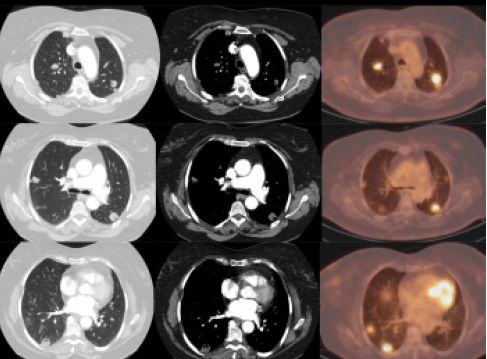

4.PET-CT

是目前较为准确的恶性肿瘤检查项目,可以较好地判断肿瘤良恶性,还能发现全身其他部位是否有转移,但尚无法替代胸部CT、支气管镜等病理检查,且费用昂贵,有时还会出现假阳性的结果,如把结核或者炎症误报成肺癌,因此临床医生常常在确诊肺癌以后用来排查远处转移时使用。